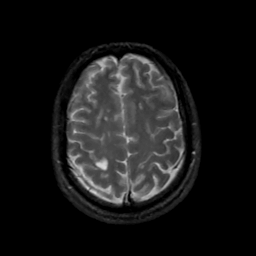

MR Study #14, June 2, 1991 -- Slice #39

[Home][Help][Clinical][Tour 1][Tour 2] Slice 39